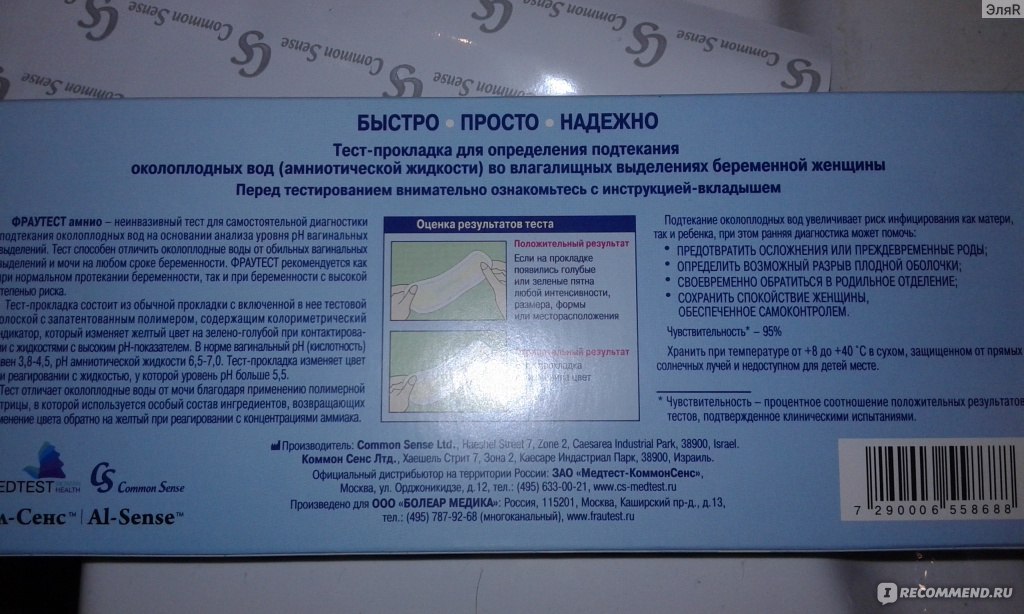

Амнион и Околоплодные Воды: Функции и Роль в Беременности